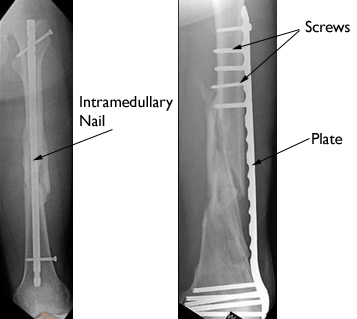

PlatesPlates are like internal splints that hold the broken pieces of bone together. They are attached to the bone with screws. Plates may be left in place after healing is complete, or they may be removed (in select cases).

ScrewsScrews are used for internal fixation more often than any other type of implant. Although the screw is a simple device, there are different designs based on the type of fracture and how the screw will be used. Screws come in different sizes for use with bones of different sizes. Screws can be used alone to hold a fracture, as well as with plates, rods, or nails. After the bone heals, screws may be either left in place or removed.

Nails or RodsIn some fractures of the long bones the best way to hold the bone pieces together is by inserting a rod or nail through the hollow center of the bone that normally contains some marrow. Screws at each end of the rod are used to keep the fracture from shortening or rotating, and also hold the rod in place until the fracture has healed. Rods and screws may be left in the bone after healing is complete. This is the method used to treat the majority of fractures in the femur (thighbone) and tibia (shinbone).

(Left) This x-ray shows a healed thighbone fracture treated with intramedullary nailing. (Right) In this x-ray, the thighbone fracture has been treated with plates and screws.